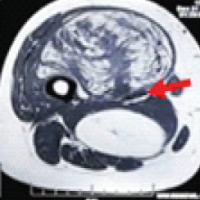

Figure 2: Computed tomography images showing a large expansile lytic lesion involving the entire metatarsal with thinning of cortices and bone grafts within the cavity.

X-ray and computed tomography show an expansile osteolytic lesion of the entire 1st metatarsal with the presence of loose pieces (bone graft from previous surgery) of bone lying within the cavity, with thin septa separating the lytic cavities, and with thinning of the cortices (Figs. 2 and 3). Routine blood chemistry was normal. The patient underwent fine needle aspiration cytology, which confirmed the diagnosis of GCT. A CT scan of the chest was done to rule out lung involvement.